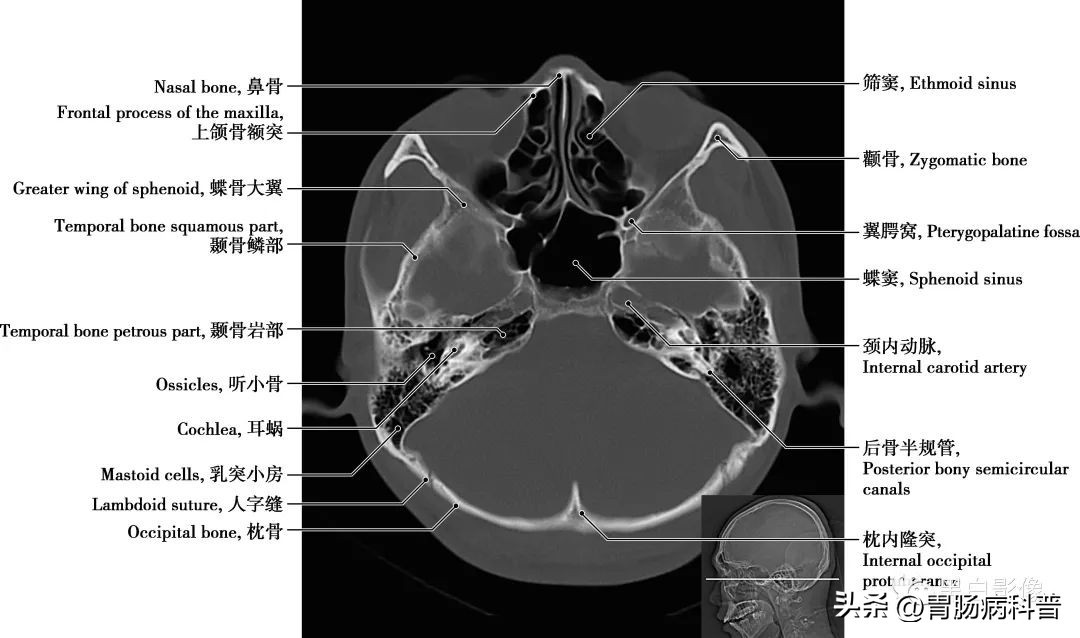

(二)骨窗轴位解剖图

图1-2-17 经第四脑室正中孔轴位切面

翼腭窝 位于颞下窝前内侧,上颌骨(或上颌窦后壁)与翼突之间,前界为上颌骨,后界为翼突及蝶骨大翼前界,顶为蝶骨体下面,内侧壁为腭骨的垂直部。窝内有颌内动脉、上颌神经及蝶腭神经节。翼腭窝向外经翼上颌裂通颞下窝,向内上经蝶腭孔通鼻腔,向前经眶下裂通眼眶,向后上经圆孔通颅中窝,借翼管通颅底外面,向下移行于腭大管、腭大孔通口腔